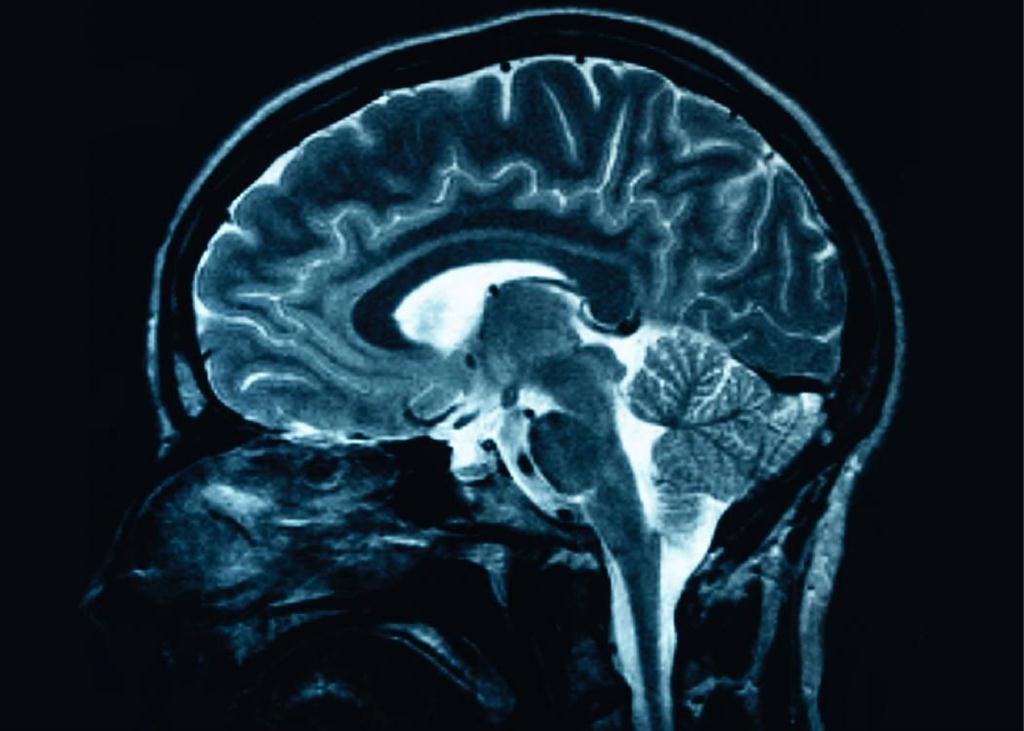

But even more astounding, chronic pain is associated with reduced brain gray matter and impaired cognitive ability to think and reason. (4) But there is good news: Reduction of chronic pain shows brain regeneration. (4)